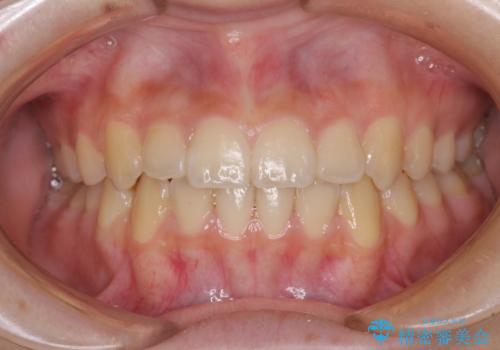

受け口傾向の咬み合わせ 前歯のデコボコをワイヤー矯正で素早く改善

この患者様もクロスバイトはあっという間に改善され、1年強で速やかに治療を終えることができました。